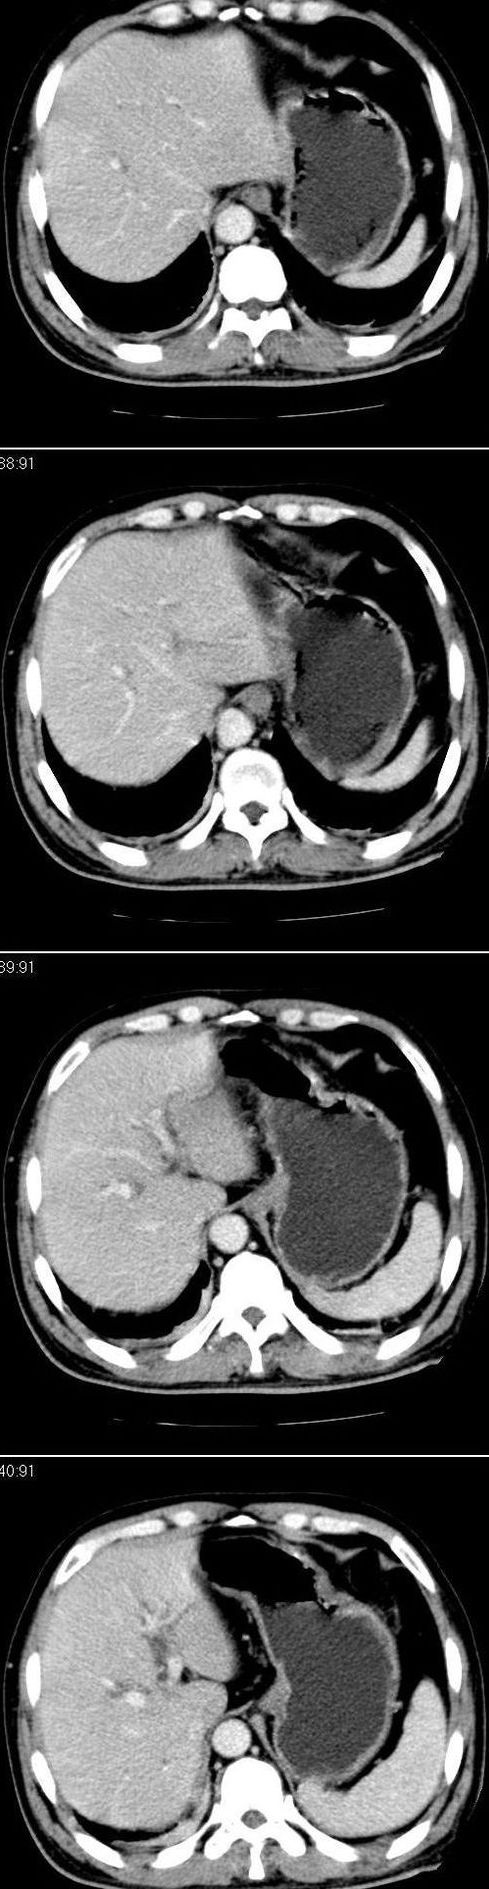

标题: CT13147:男,57岁。因胆结石阻塞性黄疸入院。 [打印本页]

标题: CT13147:男,57岁。因胆结石阻塞性黄疸入院。

男,57岁。因胆结石阻塞性黄疸入院。这是胆囊切除术后的照片,看看此片到底有什么问题。

胆总管有没有问题,尤其是肝门附近的胆总管?

肝门附近的胆总管轻度扩张 请楼主复习术前片

在手术切除胆囊的过程中,发现肝门部胆总管恶性占位,因为家属不同意手术,没有切除,能看出来么?

不是楼主提醒还真看不出来,肝内胆管扩张。略显僵硬。

肝内外胆管轻度扩张。楼主提示左右肝管合汇区域壁稍厚。胆总管末段壁似也稍厚有轻度强化。就现有资料诊断难。